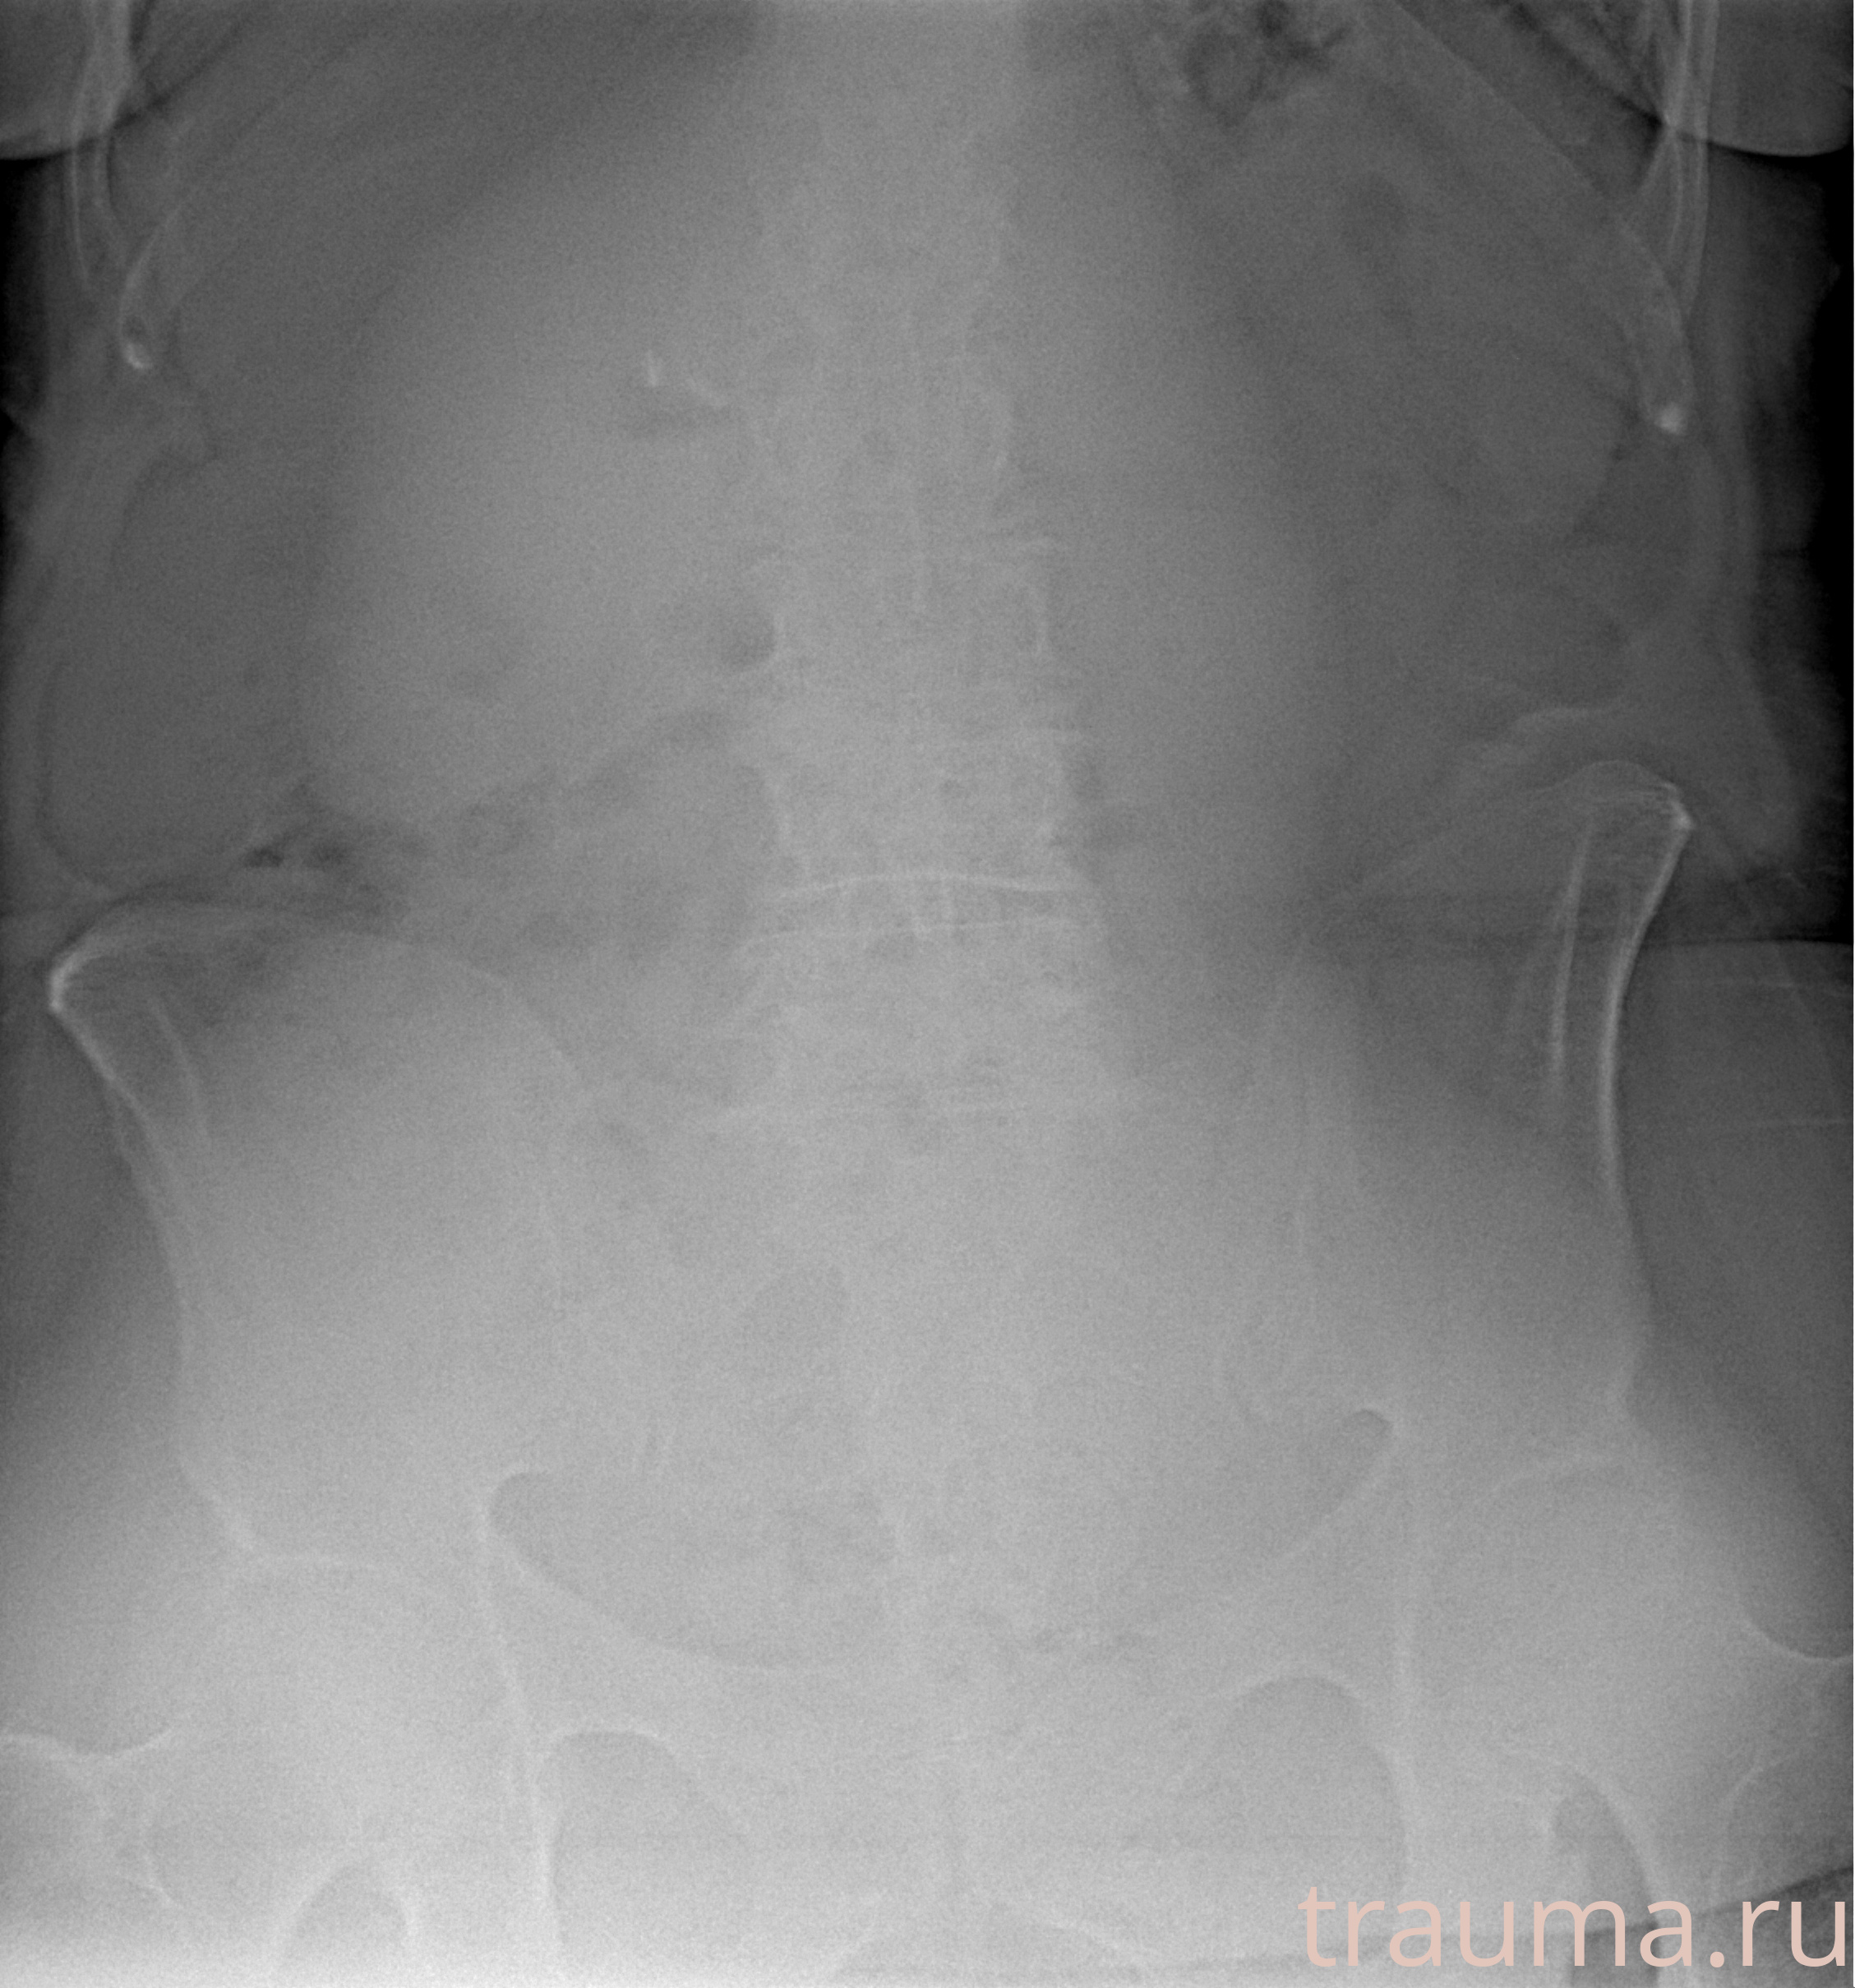

Рентген на дому: по вашему адресу приезжает врач-рентгенолог, травматолог-ортопед с мобильным рентгеновским аппаратом, проводит диагностику травмы или заболевания, делает необходимые рентгенограммы, дает рекомендации по дальнейшему лечению. Получить качественные снимки в домашних условиях возможно благодаря уникальной методике, разработанной МосРентген Центром для института  Склифосовского

при переломе шейки бедра и пневмонии от компании МосРентген Центр - партнера Института имени Склифосовского